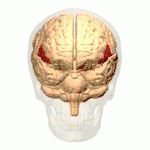

أسماء المناطق المبينة بالأرقام كما يلي:

1) القطب الجبهي ( Polus frontalis)

2) القطب القذالي ( Polus occipitalis )

3) الشق الطولاني للمخ ( Fissura longitudinalis cerebri)

4) التلفيف الجبهي العلوي ( Gyrus frontalis superior)

5) التلفيف الجبهي الوسطي ( Gyrus frontalis medius)

6) التلفيف الجبهي السفلي ( Gyrus frontalis inferior)

7) الثلم الجبهي العلوي ( Sulcus frontalis superior)

8) الثلم الجبهي السفلي ( Sulcus frontalis inferior)

9) الثلم أمام المركزي ( Sulcus praecentralis)

10) التلم المركزي ( Sulcus centralis)

11) الثلم خلف المركزي ( Sulcus postcentralis)

12) الثلم داخل الفص الجداري ( Sulcus intraparietalis)

13) الثلم الوحشي (شق سلفيوس) ( Sulcus lateralis (Fissura Sylvii))

14) التلفيف أمام المركزي ( Gyrus praecentralis)

15) التلفيف خلف المركزي ( Gyrus postcentralis)

16) الفصيص الجداري العلوي ( Lobulus parietalis superior)

17) الفصيص الجداري السفلي ( Lobulus parietalis inferior)

18) الفص القذالي ( Lobus occipitalis)

19) التلفيف الصدغي العلوي ( Gyrus temporalis superior)

20) التلفيف فوق الهامشي (؟) ( Gyrus supramarginalis)

الفص الجبهي (Frontal lobe)

الفص الصدغي (Temporal lobe)

الفص الجداري (Parietal lobe)

الفص القذالي (Occipital lobe)

الفص الحوفي (Limbic lobe)

الجَزيرَة (Insula)